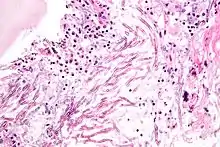

Aspergillosis. H&E stain.

The most common pathogenic species are Aspergillus fumigatus and Aspergillus flavus. Aspergillus flavus produces aflatoxin which is both a toxin and a carcinogen and which can potentially contaminate foods such as nuts. Aspergillus fumigatus and Aspergillus clavatus can cause allergic disease. Some Aspergillus species cause disease on grain crops, especially maize, and synthesize mycotoxins including aflatoxin. Aspergillosis is the group of diseases caused by Aspergillus. The symptoms include fever, cough, chest pain or breathlessness. Usually, only patients with weakened immune systems or with other lung conditions are susceptible.[1]